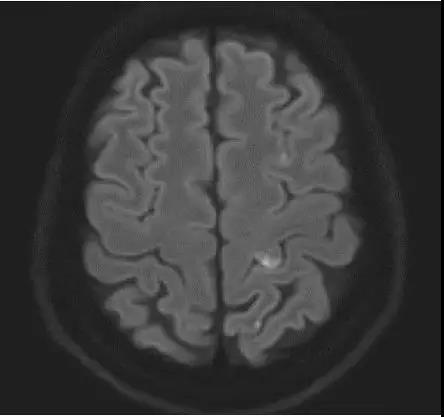

案例圖

急性腦梗死彌散加權成像